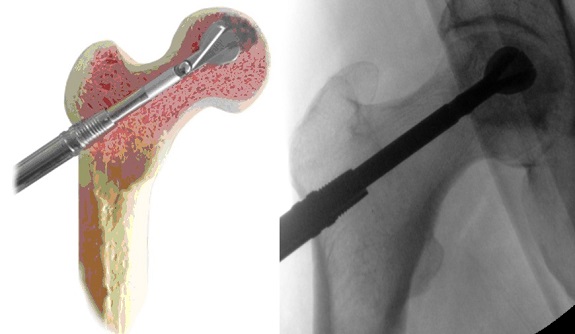

Il secondo tempo chirurgico è la procedura di core decompression con strumentario innovativo per la bonifica tridimensionale della lesione. Si esegue una piccola incisione di circa 1 cm distale al trocantere.

Sotto controllo scopico si infigge il filo di K attraverso il collo femorale fino all’area di necrosi.

Viene quindi eseguito un carotaggio di 9 mm di diametro e tramite tale accesso viene inserita una fresa manuale con una punta espandibile distale per rimuovere la lesione tridimensionale.

Infine il canale viene zaffato con un osso omologo arricchito dal concentrato cellulare midollare e PRF autologo preparato il giorno precedente l’intervento presso l’ematologia dell’istituto.